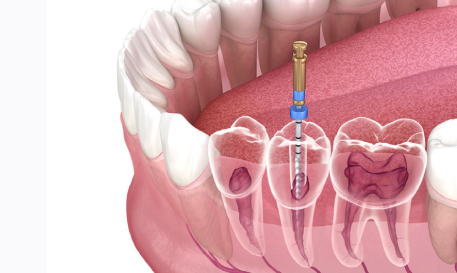

Root Canal Treatment

Removes infection and saves the natural tooth. Restores full chewing function and comfort.